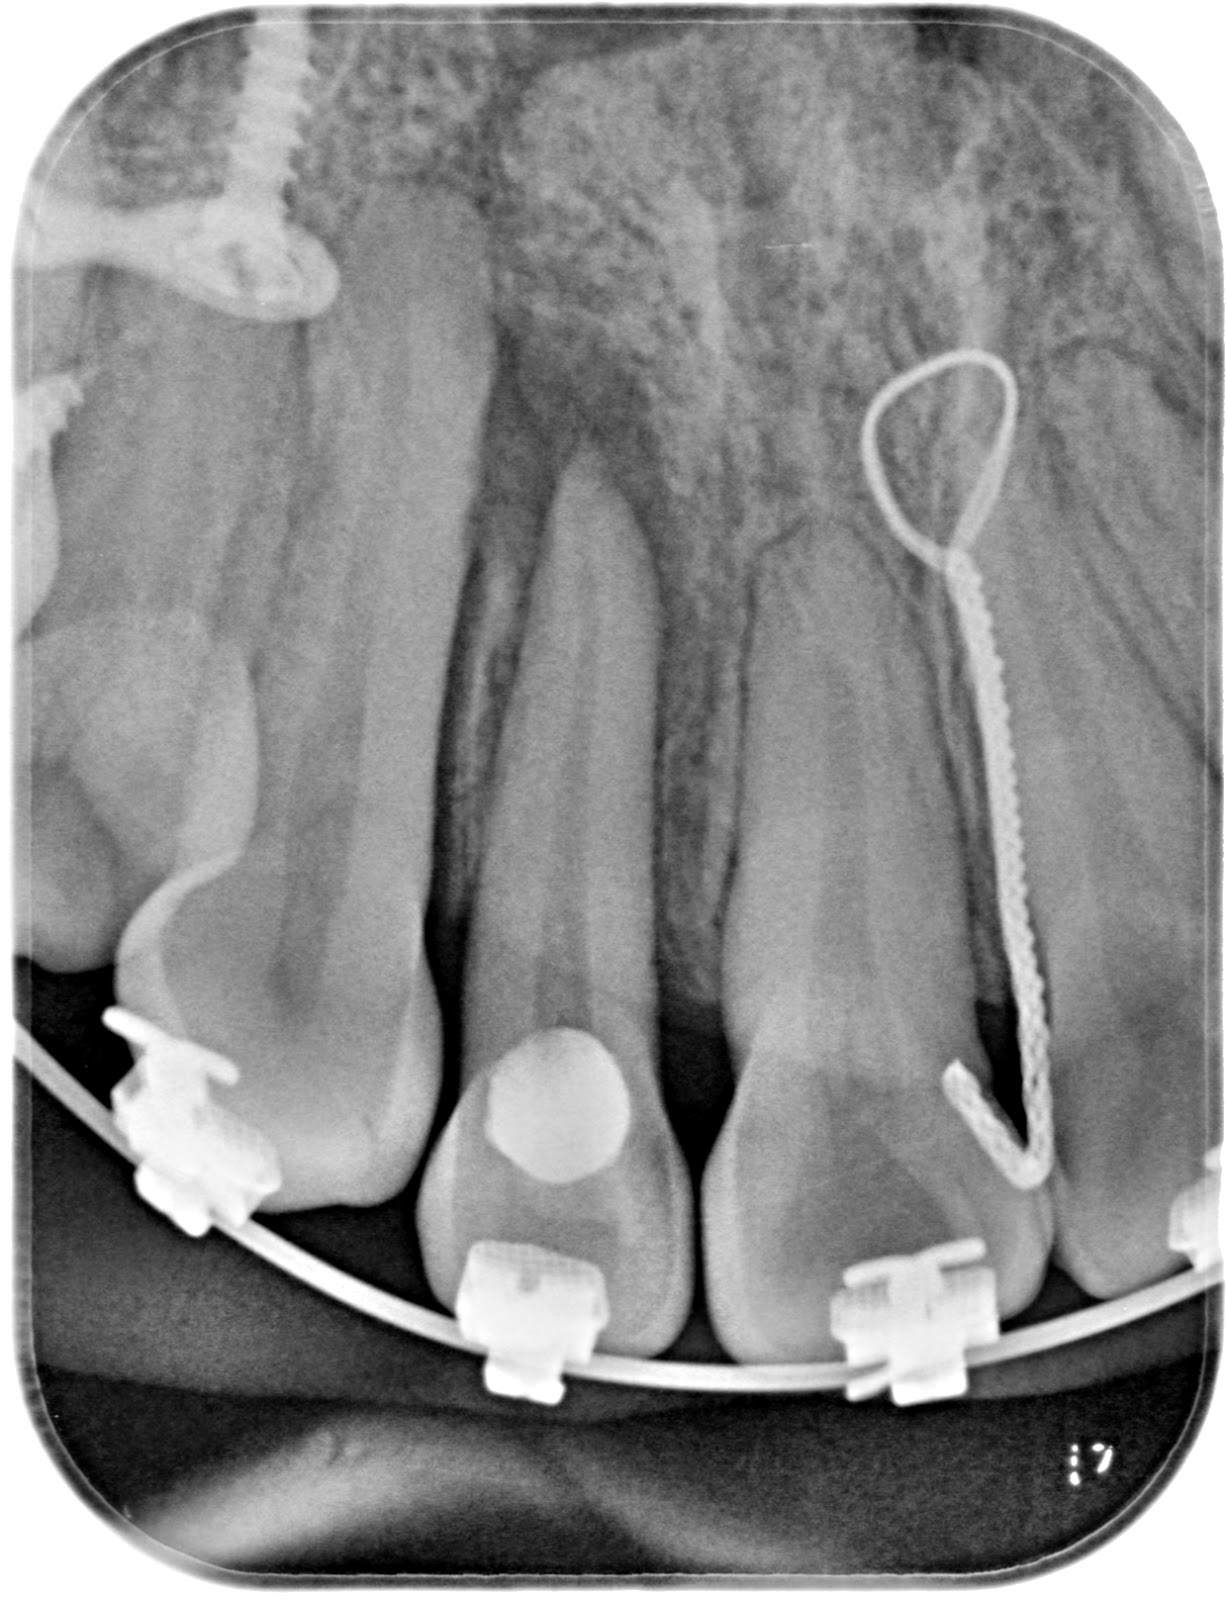

From ninacamborda.es

Barreras apicales con Biodentine Nina Camborda Endodoncista Stop Apical Endodoncia Traumatic injury to the surrounding (periapical) soft tissue should be avoided at all times. This retrospective study evaluated cases of unintentional overfillings during root canal treatment for the fate of the extruded sealer and its influence on the outcome. Stephen buchanan and christophe verbanck say that minimally invasive endodontics can be. The extent of apical enlargement can impact the outcome. Stop Apical Endodoncia.

Barreras apicales con Biodentine Nina Camborda Endodoncista Stop Apical Endodoncia The extent of the apical obturation when performing root canal therapy is a key factor that influences the success of the treatment. To this end, instrument stops should be used and instruments should be. Root canal shaping in the age of minimally invasive endodontics (mie) technology. This retrospective study evaluated cases of unintentional overfillings during root canal treatment for the. Stop Apical Endodoncia.